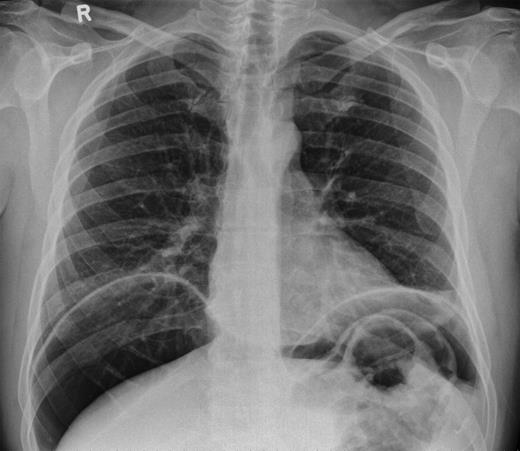

Over a year later, the same gentlemen presented to the surgical admissions unit once again with a history of acute abdominal pain. The duration and nature of symptoms were very similar to his previous admission. He again underwent plain film abdomen and erect chest radiographs that showed a large volume of free air under the diaphragm (Figs. 4 and 5).